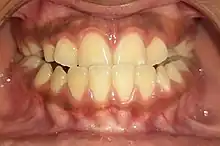

Anterior crossbite

Class 1 with anterior crossbite

An anterior crossbite can be referred as negative overjet, and is typical of class III skeletal relations (prognathism).